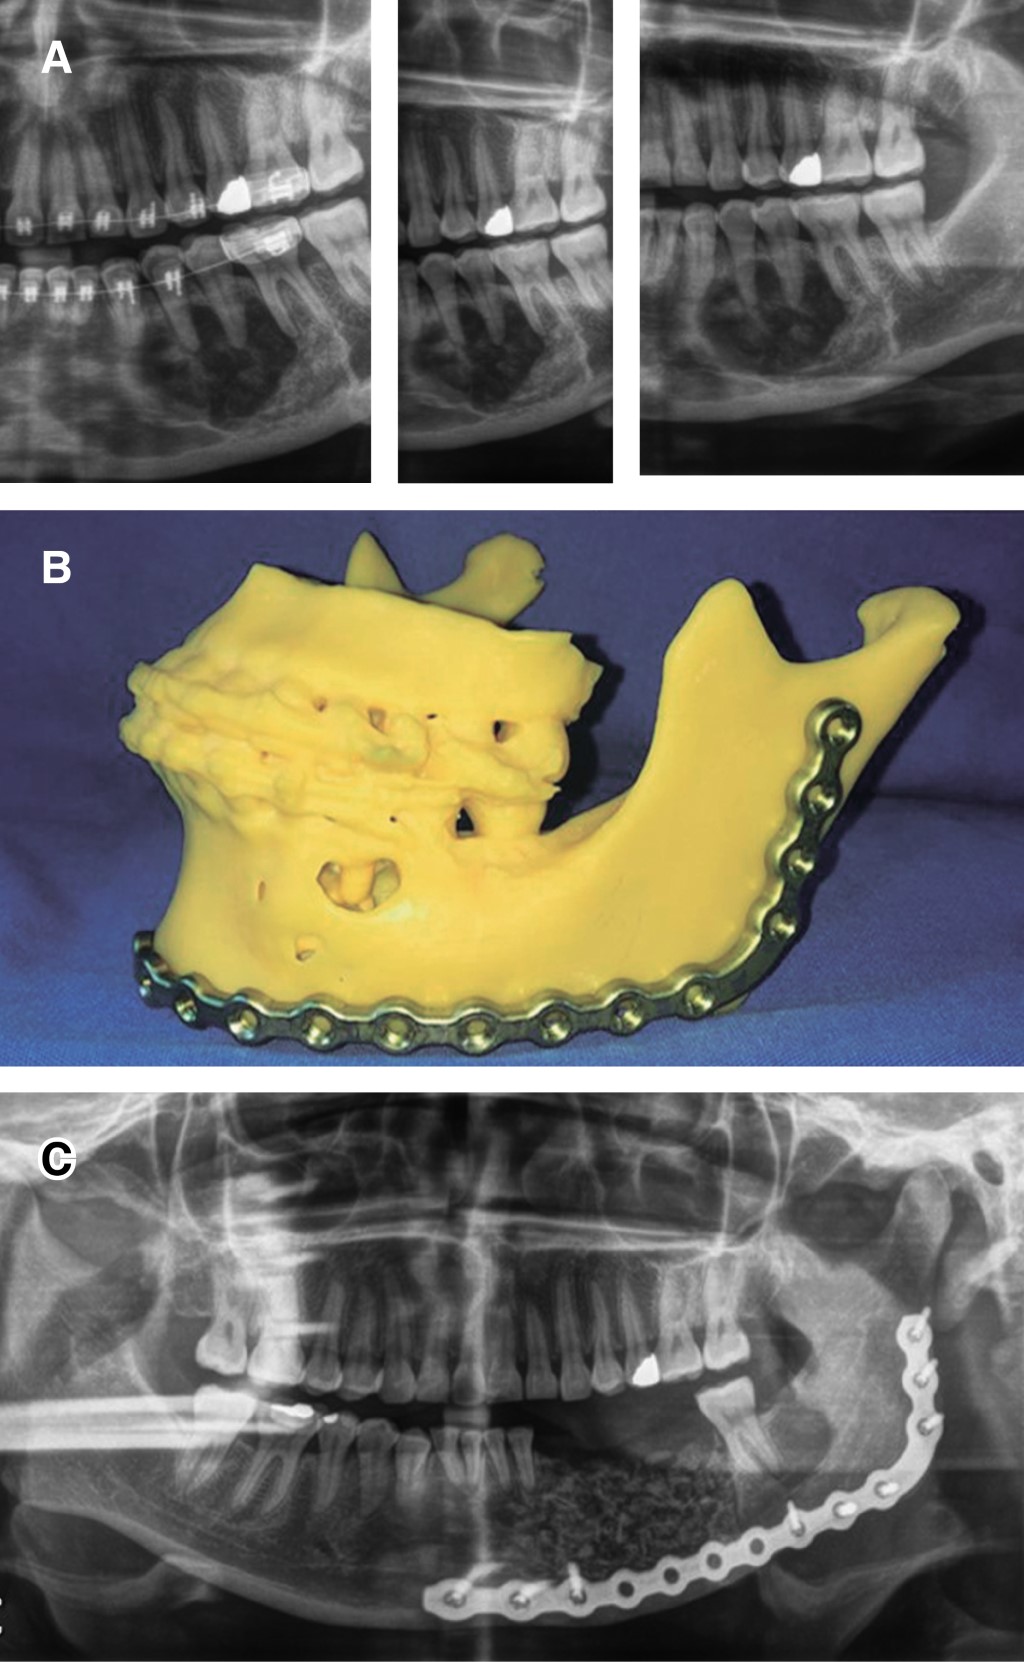

Las lesiones híbridas se consideran una patología rara que presenta elementos de diferentes entidades, cada una de las cuales tiene una categoría tumoral. En la actualidad hay menos de diez casos notificados de lesiones híbridas que muestran la asociación de una lesión central de células gigantes y un fibroma osificante. Dado que un protocolo de tratamiento para este tipo de patologías no está bien establecido en la literatura, presentamos un caso de manejo integral, incluyendo la rehabilitación, basado en la revisión de la literatura. Se trata de una paciente de 31 años con un diagnóstico inicial de lesión central de células gigantes en el cuerpo mandibular izquierdo, que fue tratada con triamcinolona intralesional, sin encontrar respuesta tras seis semanas de tratamiento, por lo que decidimos realizar una resección en bloque de la lesión y la reconstrucción simultánea con un injerto libre de cresta ilíaca anterior, obteniendo un resultado histopatológico definitivo de lesión híbrida (lesión central de células gigantes más fibroma osificante), posteriormente se realizó una rehabilitación protésica implantosoportada. En los casos de lesiones híbridas, consideramos que el manejo quirúrgico es adecuado, dado el comportamiento particular de dicha entidad que no responde adecuadamente al manejo farmacológico, recomendamos evitar el uso de medicamentos antirresortivos ya que perjudicaría el resultado de un tratamiento quirúrgico y reconstructivo posterior.

Figura 4